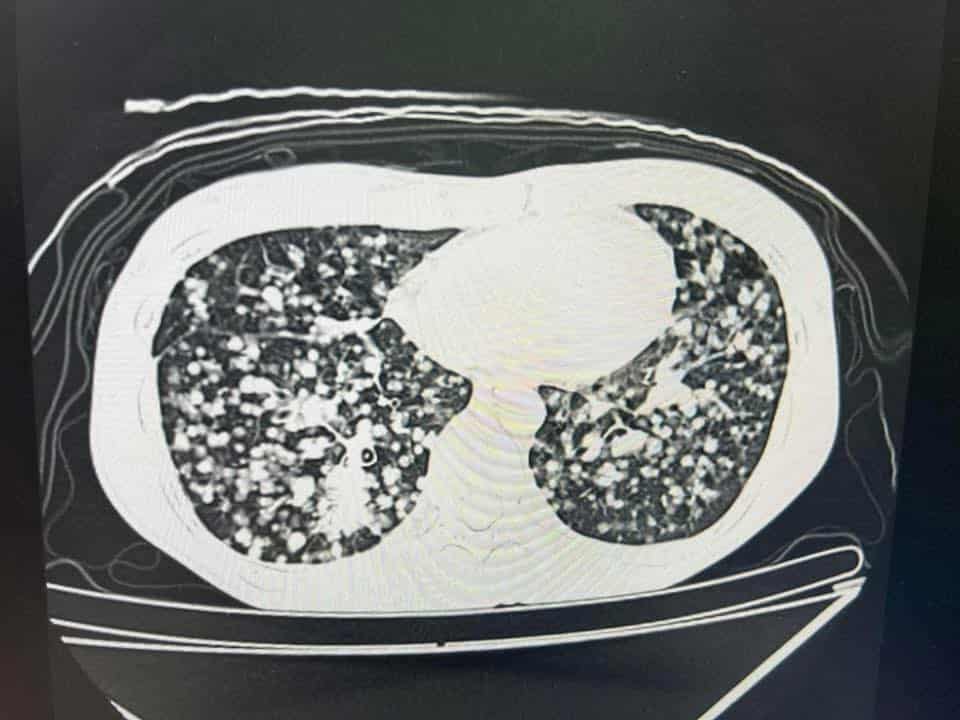

“**และนี่คือภาพปอดของออย : ก่อนทำการรักษา วันนั้นคือ ต้องนั่งรถเข็น พี่ที่ทำงานพาไป รพ. สัปดาห์ก่อนฟังผล คือ นอนไม่ได้ ต้องนั่งหลับ ไอหนักมาก แต่ยังกินข้าวได้อยู่นะ (คือเป็นคนโชคดีเรื่องกิน ไม่ว่าจะป่วยแค่ไหนก็หิวข้าว) แต่นั่นแหละ น้ำหนักก็ลดลงเรื่อยๆ เพราะน้องมะเร็งทำงานอยู่ แย่งอาหารออยไปหมด”

“มีอาการไอ หอบ เหนื่อย น้ำหนักตัวเหลือ 39 กิโล ออกซิเจนในเลือดต่ำ แอดมิทนอน รพ. วันฟังผลเลย และใช้เครื่องให้ออกซิเจนแบบแรงดันสูงช่วยในการหายใจ”